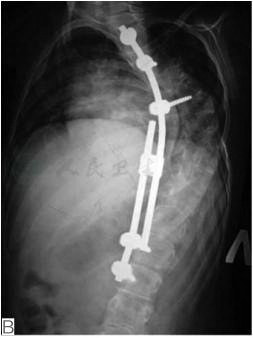

图5远端关节挛缩合并脊柱侧凸患者,6岁,女孩

A.术前全脊柱正位片提示大C型胸弯;B.行单侧可撑开型脊柱内固定手术,术后全脊柱正侧位片提示侧凸部分矫正,躯干平衡尚可;C.术后外观照(引自Komolkin I, et al. Treatment of Scoliosis Associated With Arthrogryposis Multiplex Congenita. J Pediatr Orthop, 2017,37 Suppl 1:S24-S26.)